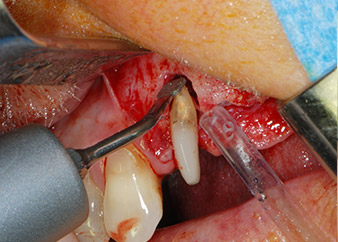

Einen Monat nach dem Eingriff waren sowohl die Schmerzen als auch die Entzündung an Zahn 24 minimal, die Zahnbeweglichkeit lag jedoch noch bei Miller-Klasse 2. Nach Freilegung und Reinigen des infizierten periapikalen und periradikulären Gewebes wurde das Ausmaß des Knochendefizits deutlich (Abb. 2 und 3).

kompletter Verlust von Knochen und Attachment

Abb. 2 und 3: Bei der Freilegung einen Monat nach endodontischer Revision und Beginn einer systematischen Parodontalbehandlung weist die bukkale Wurzel des Zahns 24 einen kompletten Verlust von Knochen und Attachment auf.

Zunächst wurde in einem Versuch, das Paro-Endo-Problem zu lösen, an der verbleibenden Wurzeloberfläche ein vorsichtiges Debridement mit einem piezochirurgischen Gerät vorgenommen (Piezomed, W&H) (Abb. 4); dann wurde der Apex mit dem gleichen Instrument im Sinne einer WSR abgetragen, um das verbleibende infizierte apikale Gewebe zu entfernen (Abb. 5). Eine retrograde Füllung war nicht notwendig, da die orthograde Füllung gerade revidiert worden war.

Abb. 4: Um den Zahn 24 als vorläufigen Brückenpfeiler zu erhalten, wird das Parodont mit einem piezochirurgischen Sytem gereinigt ...

bukkale Wurzelspitze

Abb. 5 ... und die bukkale Wurzelspitze mit dem gleichen Instrument abgetragen (WSR).